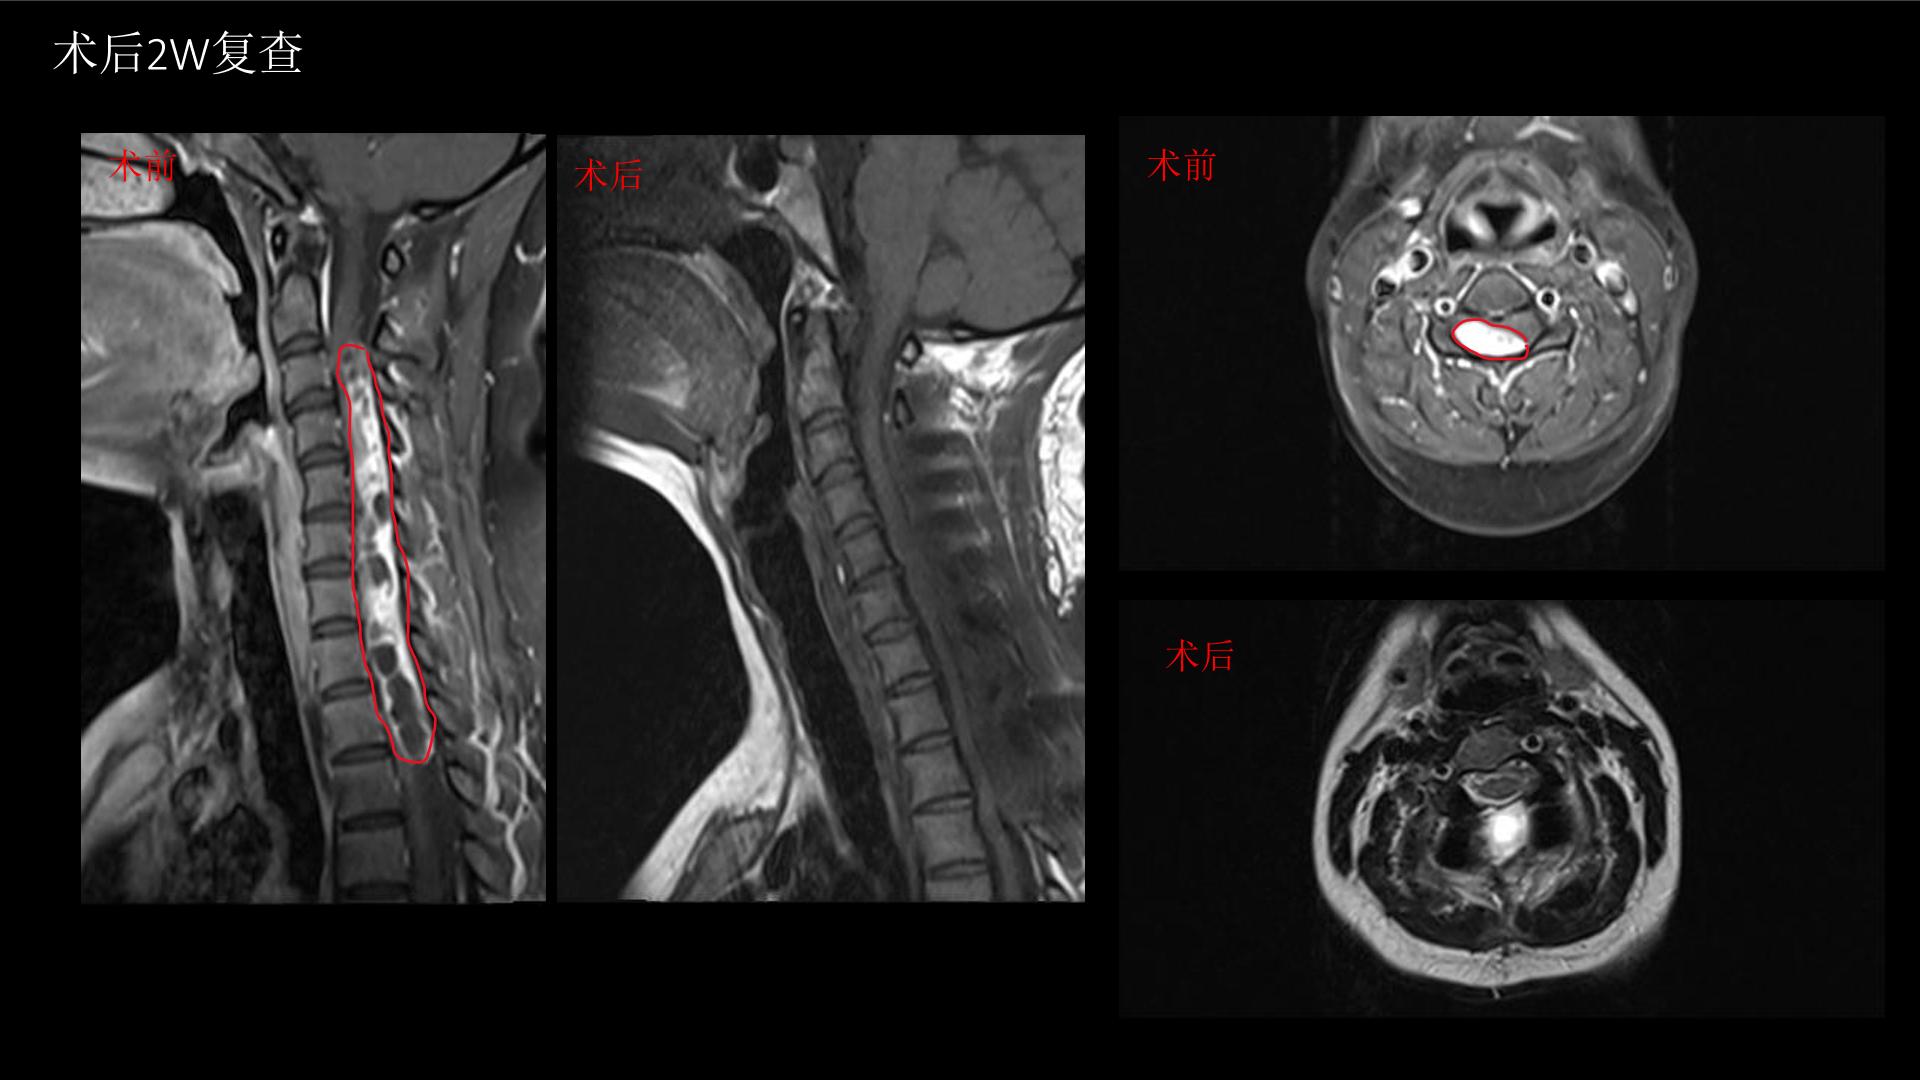

西安交通大学第二附属医院刘重霄教授团队:一例巨长型颈胸椎神经鞘瘤切除术+脊柱内固定术